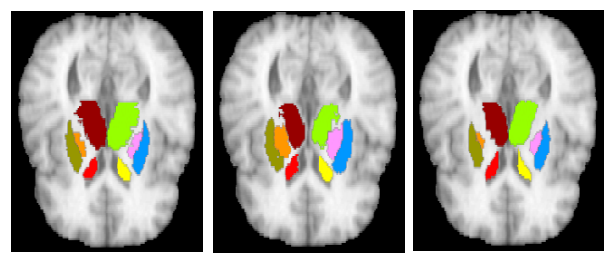

Refer to caption

Fig. 3: 2D slice segmentation (IBSR). Left: Groundtruth. Middle: RF-based results. Right: CNN-based results.

In the second experiment, we compare the accuracy of our proposed method with two publicly available state-of-the-art automatic segmentation toolboxes, Freesurfer [10], and FSL-FIRST [11]. In Table 2 we report the average Dice coefficient for the left and right structures; these results show that our method provides better segmentations compared to the state-of-the-art for three sub-cortical structures in both IBSR and RE dataset. However, Freesurfer results in better segmentation for caudate in the IBSR dataset which could be attributed to the limitation of CNN in capturing thin tail areas of the caudate structures. In Figure 3 we show qualitative results.